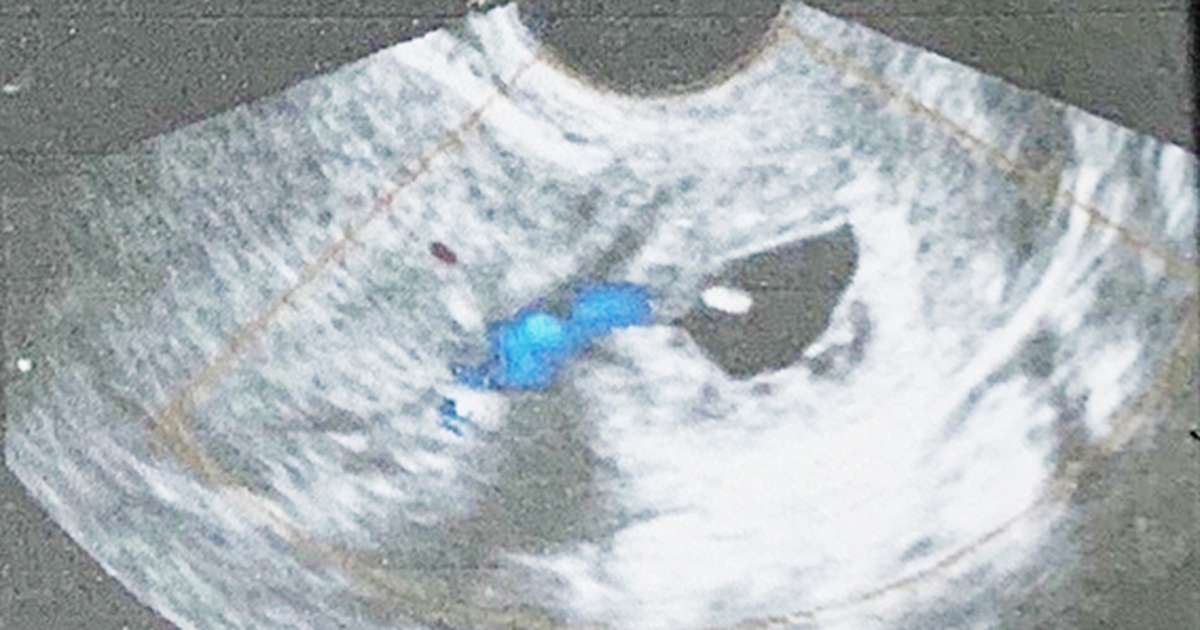

Chị B.N.N (27 tuổi, Bình Dương) phát hiện trễ kinh nên thử thai bằng que, phát hiện mình có thai. Tuy nhiên, thai lại sống ở ngay cổ tử cung, buộc bác sĩ phải chấm dứt thai kỳ để cứu thai phụ.